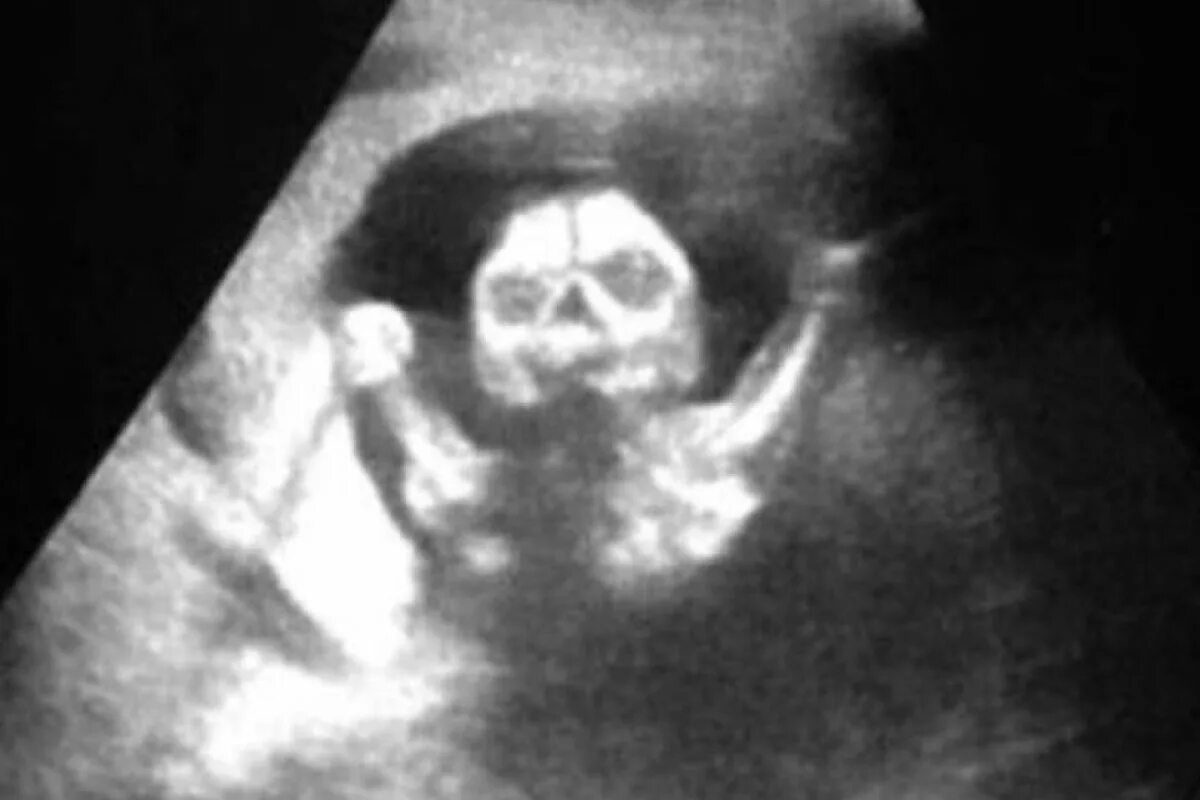

Ребенок исчез во время узи как называется